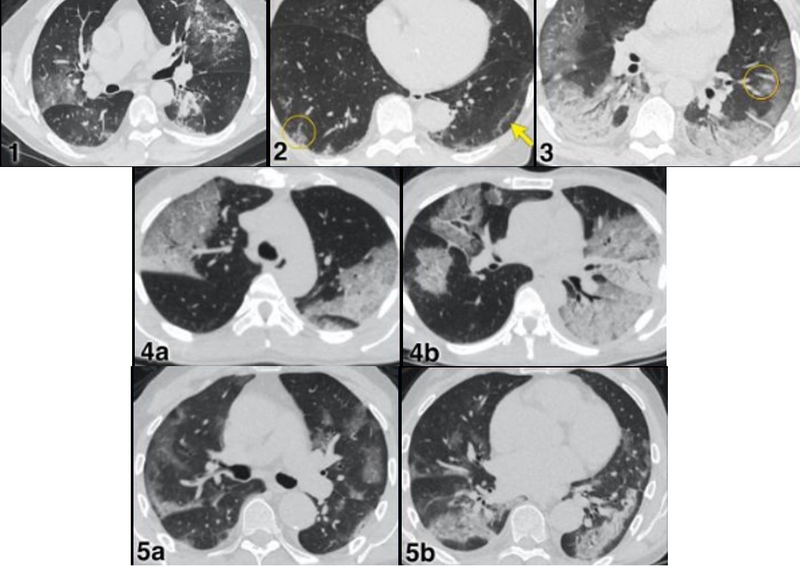

Chụp CT phổi là kỹ thuật sử dụng tia X kết hợp với hệ thống máy tính để tạo ra hình ảnh cắt lớp chi tiết của phổi và các cấu trúc lân cận. Khác với chụp X quang thông thường, hình ảnh CT cho phép quan sát phổi ở nhiều lát cắt khác nhau giúp phát hiện những tổn thương rất nhỏ mà X quang có thể bỏ sót.

Kỹ thuật này có thể thực hiện dưới dạng CT phổi thường hoặc CT phổi có tiêm thuốc cản quang tùy mục đích chẩn đoán. Nhờ độ phân giải cao, CT phổi giúp đánh giá chính xác nhu mô phổi, phế quản, mạch máu và hạch trung thất.

CT phổi độ phân giải cao là công cụ quan trọng giúp chẩn đoán các bệnh phổi kẽ như xơ phổi, viêm phổi kẽ hoặc bệnh phổi do tự miễn.

CT phổi là phương pháp rất hiệu quả trong phát hiện tổn thương nghi ngờ ung thư phổi, đặc biệt ở giai đoạn sớm. Tuy nhiên, chẩn đoán xác định vẫn cần kết hợp sinh thiết và các xét nghiệm chuyên sâu khác.

Bên cạnh đó, hình ảnh CT còn giúp bác sĩ đánh giá kích thước khối u, mức độ lan rộng và hỗ trợ theo dõi hiệu quả điều trị qua từng giai đoạn.